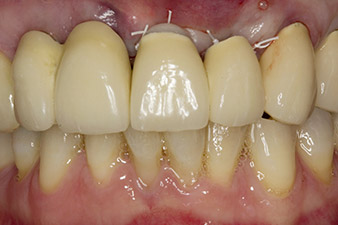

Abb. 6: Situation nach Implantation und Augmentation: Die alte Brücke wird für die Einheilphase wieder als Provisorium eingegliedert, mit frei geschliffenem Brückenglied an der Implantatposition 22. Als definitiver Ersatz ist eine Zirkonoxidbrücke von 12 auf das noch zu inserierende Implantat an Position 23 geplant.

Im Fallbeispiel wurde die Situation im ersten Eingriff mit einem Implantat an Position 22 gelöst, und einem weiteren an der Position des im weiteren Verlauf extrahierten Zahnes 23. Das zweite Implantat folgt nach Osseointegration von Implantat 22. Die umgearbeitete Brücke wurde bis zur Einheilung von Implantat 23 und der Abformung für den definitiven Zahnersatz wieder eingegliedert. Vorteile dieses abgestuften Vorgehens sind eine sichere Belastbarkeit der Implantate und gut ausgereifte Hart- und Weichgewebe (5).